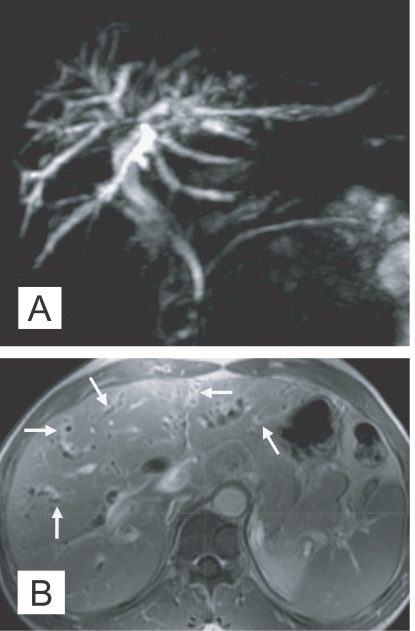

The imaging findings of clonorchiasis-associated cholangiocarcinomas are combinations of the findings of the 2 diseases (Figs. 5 and 6) (Choi et al., 2004). Diffuse dilatation of peripheral intrahepatic ducts is attributed to changes that are secondary to clonorchiasis, and segmental and severe dilatation around the tumor is caused by obstruction by the tumor (Fig. 5) (Choi et al., 1988 & 1989). Extrahepatic cholangiocarcinomas, associated with clonorchiasis, show diffuse dilatation of the peripheral and central intrahepatic bile ducts (Fig. 6). When an extrahepatic cholangiocarcinoma is not associated with clonorchiasis, dilatation of the peripheral intrahepatic bile ducts is not conspicuous (Fig. 7). After the development of the distal obstruction due to an extrahepatic cholangiocarcinoma, pre-existent dilated intrahepatic bile ducts with clonorchiasis easily progress the dilatation.

Fig. 6

Cholangiocarcinoma in the mid common duct, with clonorchiasis, in a 64-year-old man. A. MR cholangiography shows a diffuse dilatation of the intrahepatic bile ducts and common duct. Note an intraluminal tumor (arrows) at the level of the mid common duct. B. Contrast-enhanced CT shows diffuse and marked dilatation of the intrahepatic bile ducts. C. CT at a level lower than (B) shows the enhancing, segmental thickened wall (arrows) of the mid common duct, which represents an extrahepatic cholangiocarcinoma.

Fig. 7

Cholangiocarcinoma in the mid common duct, without clonorchiasis, in a 65-year-old woman. A. MR cholangiography shows an intraluminal tumor (arrows) at the level of the mid common duct. B. Contrast-enhanced CT shows minimal dilatation of the central intrahepatic duct (arrows), but the peripheral intrahepatic ducts are not dilated. C. CT at a level lower than (B) shows the enhancing, segmental thickened wall (arrows) of the mid common duct, which represents an extrahepatic cholangiocarcinoma.

Fig. 6 Cholangiocarcinoma in the mid common duct, with clonorchiasis, in a 64-year-old man. A. MR cholangiography shows a diffuse dilatation of the intrahepatic bile ducts and common duct. Note an intraluminal tumor (arrows) at the level of the mid common duct. B. Contrast-enhanced CT shows diffuse and marked dilatation of the intrahepatic bile ducts. C. CT at a level lower than (B) shows the enhancing, segmental thickened wall (arrows) of the mid common duct, which represents an extrahepatic cholangiocarcinoma.

Fig. 7 Cholangiocarcinoma in the mid common duct, without clonorchiasis, in a 65-year-old woman. A. MR cholangiography shows an intraluminal tumor (arrows) at the level of the mid common duct. B. Contrast-enhanced CT shows minimal dilatation of the central intrahepatic duct (arrows), but the peripheral intrahepatic ducts are not dilated. C. CT at a level lower than (B) shows the enhancing, segmental thickened wall (arrows) of the mid common duct, which represents an extrahepatic cholangiocarcinoma.